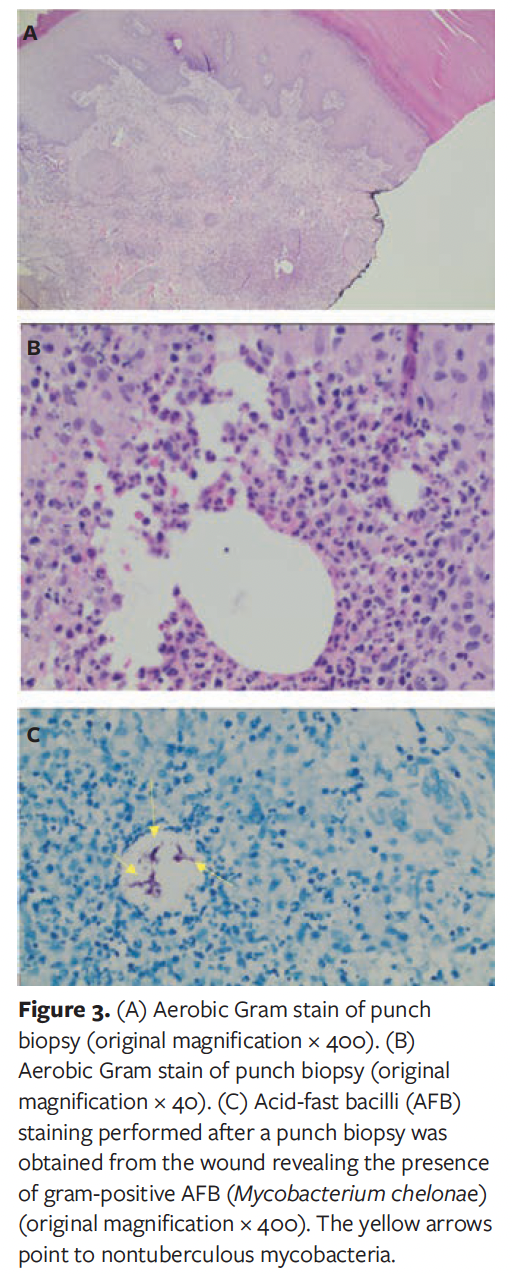

Following her second hospitalization, the patient received several intravenous antibiotics—initially vancomycin and piperacillin/tazobactam. During this hospitalization, a repeat deep soft tissue culture was sent for analysis and revealed “possible actinomyces.” Due to this finding, the patient was transitioned to intravenous penicillin daily via a peripherally inserted catheter line for 6 weeks in the outpatient setting. However, even with this antibiotic regimen, her wounds continued to increase in size for 3 weeks to 4 weeks and then stabilized. Because these wounds increased in size over the month-long period, and because they did not heal over an 8-week period, it was suggested that the patient be readmitted to the hospital for further workup, including a punch biopsy, possibly followed by discharge to subacute rehabilitation to help aid in strict non-weight bearing status to the left lower extremity. The need for a punch biopsy was secondary to other concerning diagnoses, including Marjolin ulcer or squamous cell carcinoma. During the patient’s third hospitalization, a tissue culture from a 3-mm punch biopsy was sent, along with tissue for microbiology for aerobic, anaerobic, fungal, and AFB cultures. AFB smears revealed the presence of AFB (Figure 3). The patient was then transferred to a tertiary hospital for further antibiotic and wound care recommendations.

At transfer, the patient’s history was reviewed, again revealing no recent surgeries and no changes to her daily routine, including no recent travels outside of Canada and the United States or unique sick contacts. The patient had stated that she was in good health, with the only immunosuppressive condition being diabetes mellitus, which was well controlled, with A1c of 5.5%. Further workup was initiated, including an interferon gamma release assay for tuberculosis, which was negative. Her chest radiograph showed no pathology. AFB culture from previously obtained foot biopsy grew M chelonae after 10 days; susceptibility testing results were returned after 14 more days (Figure 4). After consultation with infectious diseases specialists, a 4-month course of oral linezolid 600 mg daily and oral clarithromycin 500 mg twice daily was recommended, as well as silver alginate dressing changes. After 10 weeks of this treatment regimen, the patient’s wounds healed (Figure 5).